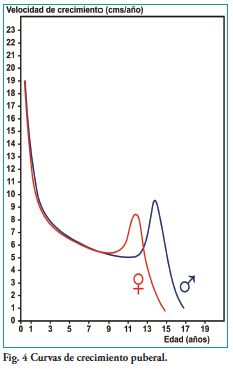

Todas las glándulas endócrinas influyen en el crecimiento y desarrollo, pero el rol principal sobre el crecimiento se atribuye a la somatotrofina u hormona del crecimiento (GH, growth hormone). La somatotrofina aumenta el crecimiento óseo en longitud al estimular los cartílagos de conjugación de los huesos largos y actuar sobre las sincondrosis basicraneales. Por otro lado estimula la formación ósea a nivel del periostio. La acción de esta hormona es importante en el desarrollo del cráneo (16) y del cartílago condilar de las articulaciones témporo-mandibulares, además de los estímulos funcionales (17). Los efectos fisiológicos de esta hormona no se ejercen a través de ninguna glándula efectora, sino que a diferencia de otras hormonas hipofisarias tiene una acción directa sobre la mayoría de los tejidos del organismo. Además de estimular el crecimiento corporal, ejerce múltiples efectos metabólicos específicos como: aumentar la síntesis de proteínas en casi todas las células del organismo; favorecer la movilización de ácidos grasos del tejido adiposo, incrementando la cantidad de ácidos grasos libres en la sangre para su utilización como fuente de energía; y disminuir la cantidad de glucosa captada por las células. Bajo la influencia de una cantidad excesiva de hormona de crecimiento, la movilización de las grasas del tejido adiposo puede ser tan elevada que el hígado forme grandes cantidades de ácido acetoacético y al liberarlo a los líquidos corporales cause cetosis (7). La somatotropina no afecta el crecimiento fetal ni es importante en los primeros meses de vida. Resulta esencial para la tasa normal de desarrollo del cuerpo durante la niñez y la adolescencia. La GH es segregada por la hipófisis anterior durante toda la vida y continúa siendo importante desde el punto fisiológico incluso después de que cesa el crecimiento. Es uno de los factores fisiológicos que contrarresta y de esta forma modula algunas de las acciones de la insulina sobre el músculo, el tejido adiposo, el hígado y los tejidos periféricos. La somatotropina, al igual que las hormonas glucocorticoideas, tiene un efecto inhibidor tónico sobre las acciones de la insulina. A su vez la hiperglucemia inhibe la secreción de GH, mientras que la disminución de la concentración de la glucosa en plasma estimula la secreción de GH (9). El metabolismo de la glucosa que estimula la secreción de insulina es inversamente proporcional a la hormona de crecimiento y/o los niveles de factor de crecimiento similar a la insulina. La hormona de crecimiento reduce la sensibilidad puberal a la insulina.

La creencia que el deterioro del control metabólico en adolescentes con diabetes tipo 1 era sólo el resultado de los factores conductuales y psicosociales característicos de esta etapa no considera la importancia de los cambios fisiológicos del metabolismo y la sensibilidad a la insulina. Los requisitos insulínicos aumentan entre un 30 y 50% durante la pubertad en estos pacientes al aumentar la insensibilidad a la insulina, por ser mayor la secreción de la hormona

de crecimiento y los esteroides sexuales en esta etapa de la vida. La dosis diaria de insulina administrada se debe incrementar durante la pubertad por la mayor resistencia a la insulina en este período relacionada con los altos niveles circulantes de hormona de crecimiento (18).

En el diseño de estudios sobre crecimiento se puede hacer una investigación longitudinal a través de mediciones repetidas en el mismo sujeto o un estudio transversal donde se miden distintos niños de la misma edad. Por otra parte, es posible calcular la edad promedio a la cual se presenta el pico de crecimiento puberal rápido (19).

Holl y col. demostraron una reducción significativa de talla en pacientes pediátricos con inicio de diabetes tipo 1 en la etapa prepuberal. El control metabólico insuficiente se relaciona con menor ganancia de talla en niños diabéticos de ambos sexos. Las niñas con diagnóstico prepuberal de diabetes tipo 1 sin adecuado tratamiento, además de padecer reducción del crecimiento en altura tienen tendencia al sobrepeso a partir del inicio de la pubertad.

Sin embargo en las niñas la talla final alcanzada registra una ligera pérdida de ganancia respecto a los valores de normalidad, en comparación con la mayor pérdida que sufren los varones (21).

La maduración sexual es más tardía en las niñas diabéticas tipo 1 respecto a niñas sin esta patología, con edad de menarca posterior a la edad promedio. La maduración sexual en varones también está retardada (19).

El buen control metabólico del paciente niño y adolescente con diabetes tipo 1 mejorará el pronóstico de ganancia de talla, lo cual representa una importante motivación del paciente y sus familiares en lograr dicho objetivo. La edad de inicio y duración de la enfermedad influyen en el crecimiento de estos niños. La estatura alcanzada por los pacientes diagnosticados antes de la pubertad es menor que la de los pacientes con inicio de la enfermedad en edades puberales o pospuberales. A mayor evolución de la enfermedad menor será la ganancia de talla en ambos sexos. El crecimiento y desarrollo normal es uno de los logros del tratamiento de los pacientes con diabetes tipo 1 desde fases iniciales de la enfermedad. El odontólogo puede mejorar el control metabólico de pacientes diabéticos al mantener en óptimas condiciones la salud bucal.